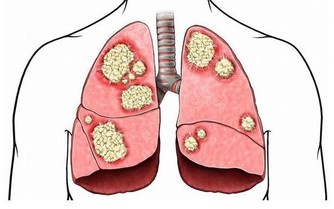

熏臘、腌制的食品含較多亞硝胺,亞硝胺在酒精中的溶解度很大,會增加患食管癌、胃癌等的風險。

胡蘿蔔中含有豐富的胡蘿蔔素, 如果喝酒時吃大量胡蘿蔔,容易產生肝毒素,誘發肝病。